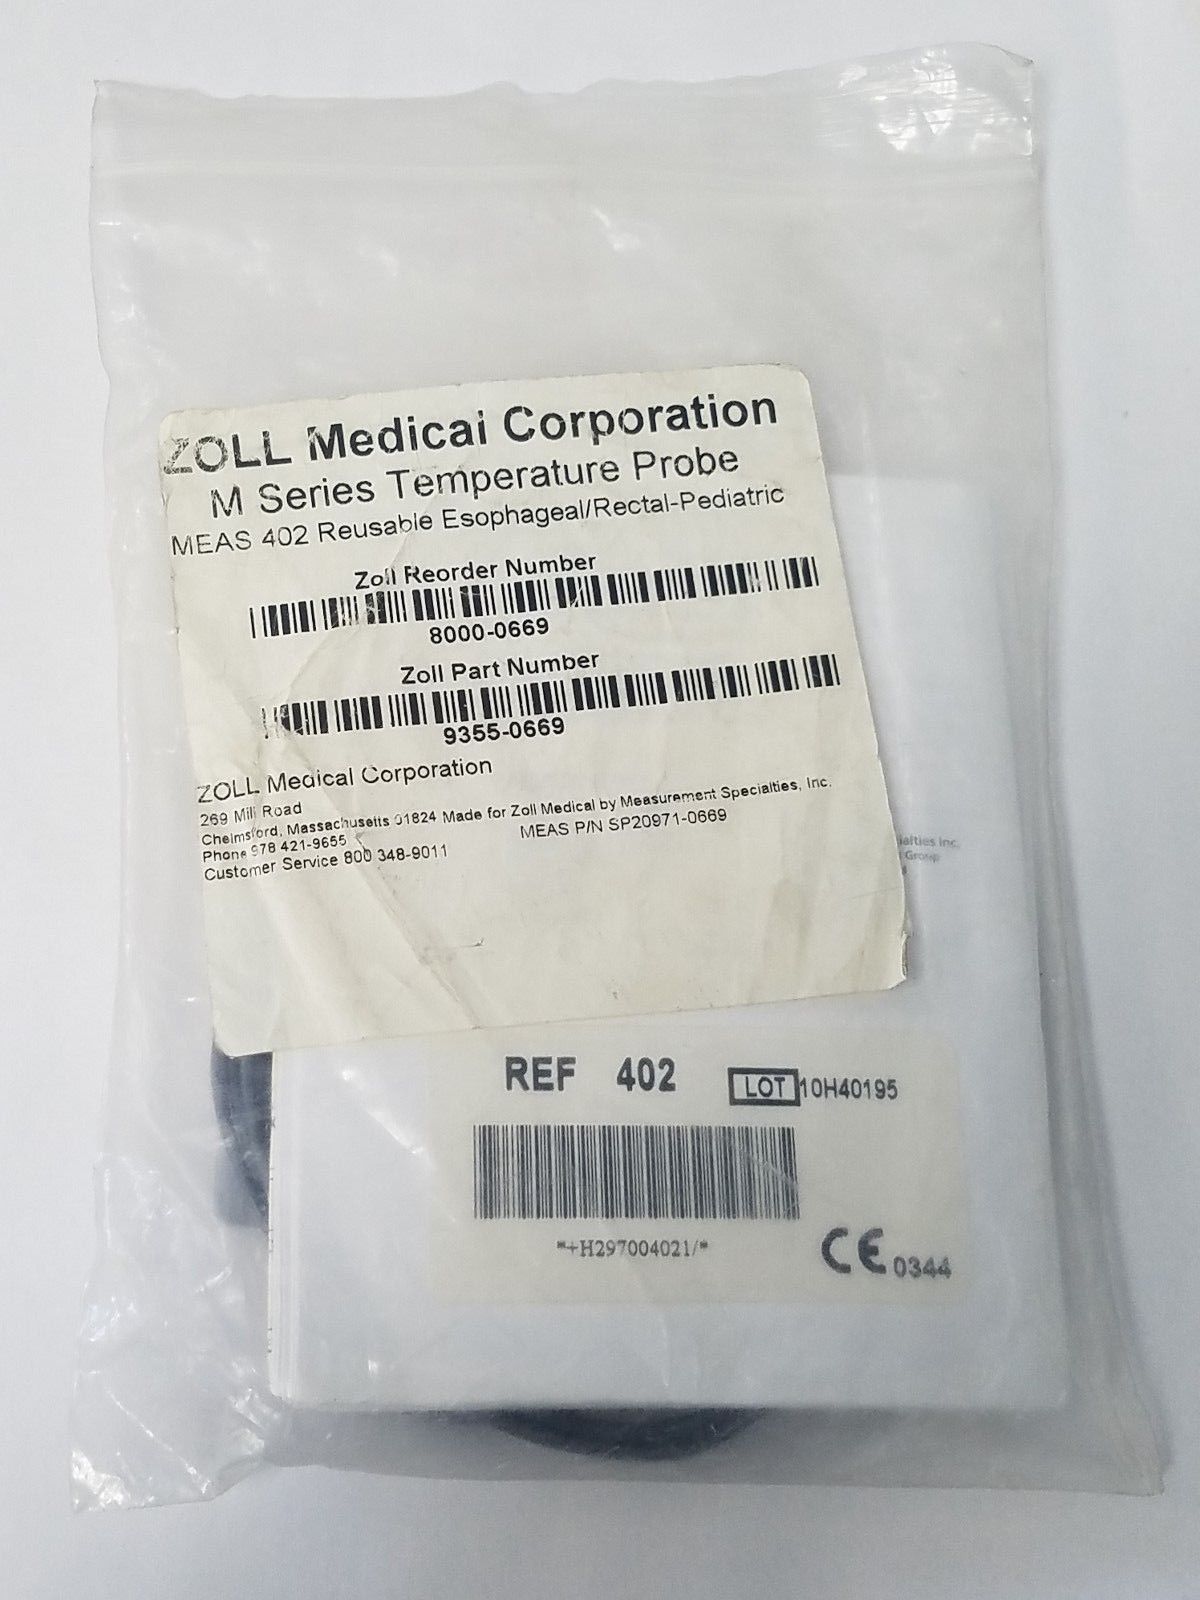

Zoll M Series Temperature Probe MEAS 402 Reusable Esophageal / Rectal Pediatric

Sale price$ 78.71

Regular price$ 95.99